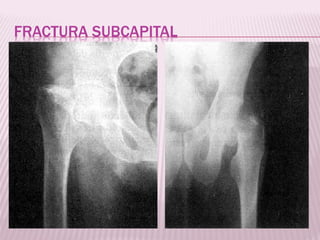

FRACTURA SUBCAPITAL

 Aquellas producidas en un plano

inmediatamente inferior al borde del cartílago

articular, generalmente tiene una orientación

oblicua de modo que compromete un

segmento pequeño de cuello del fémur.